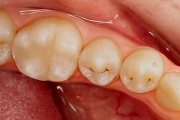

kaaries igemeäärel

kaaries